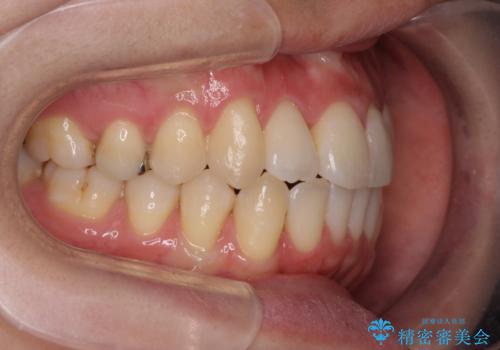

引っ込んだ前歯を並べたい マウスピースと部分ワイヤーのコンビネーション矯正

- 引っ込んで生えてしまっている前歯を並べたい、と矯正治療を希望され来院されました。

まずマウスピース矯正インビザラインシステムで、引っ込んだ歯が並ぶためのスペースを作ったのち、部分ワイヤー矯正を行い短期間での配列を計画します。

マウスピース・ワイヤーそれぞれの長所をうまく活かすことで治療期間の短縮が可能となります。

このように前歯の部分ワイヤーは引っ込んでしまった前歯や がたつきを素早く改善することができます。